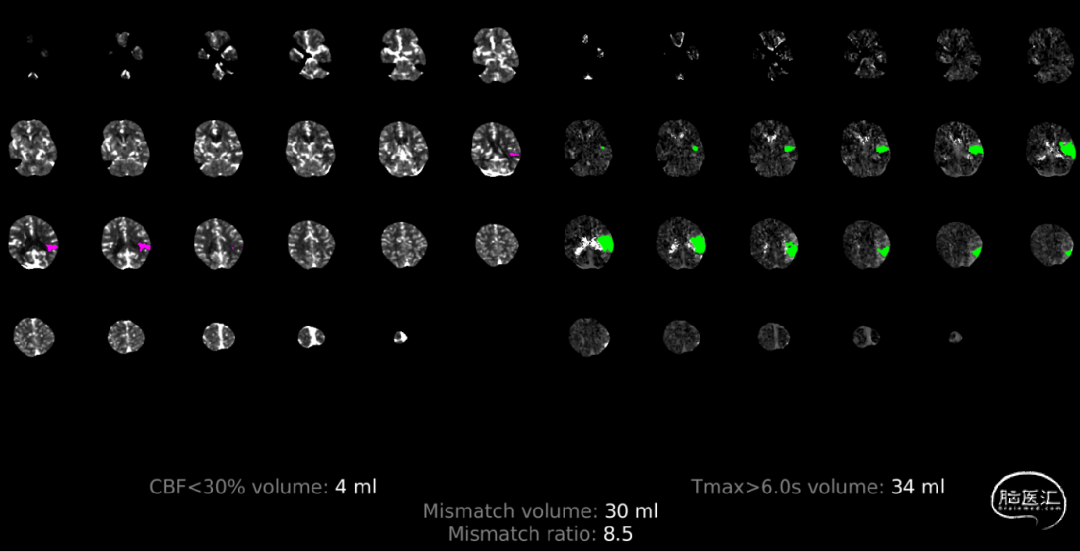

RAPID提示Mismatch 30ml。